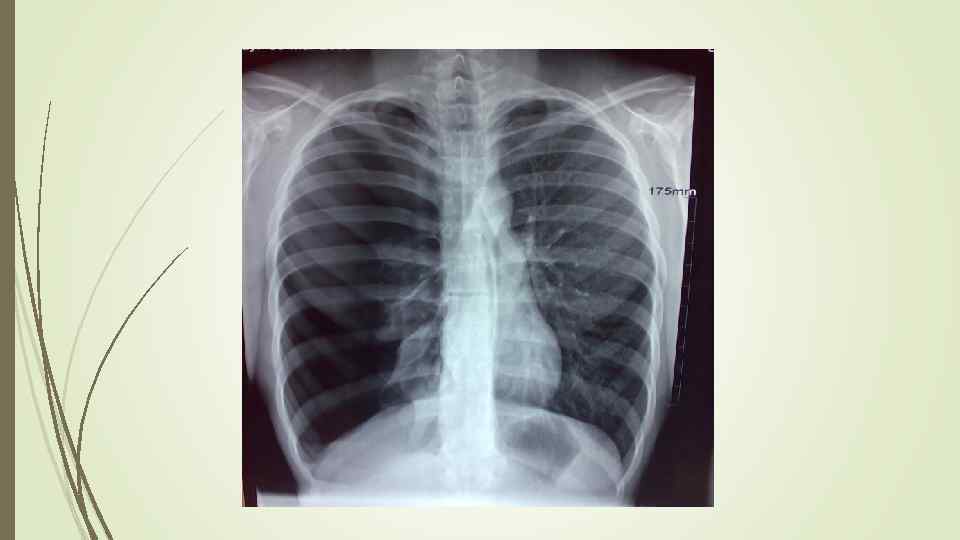

Бронхопневмония Характерно наличие двухсторонних множественных очаговых теней. Контуры очагов нечеткие, интенсивность тени небольшая. Инфильтрация неоднородна. Мелкие, малоинтенсивные очаги не всегда выявляются на снимках. Легочный рисунок усилен на всем протяжении легких. Корни расширены, не структурны. Как правило, отмечается реакция плевры, могут быть и экссудативные плевриты.

Бронхопневмония Характерно наличие двухсторонних множественных очаговых теней. Контуры очагов нечеткие, интенсивность тени небольшая. Инфильтрация неоднородна. Мелкие, малоинтенсивные очаги не всегда выявляются на снимках. Легочный рисунок усилен на всем протяжении легких. Корни расширены, не структурны. Как правило, отмечается реакция плевры, могут быть и экссудативные плевриты.